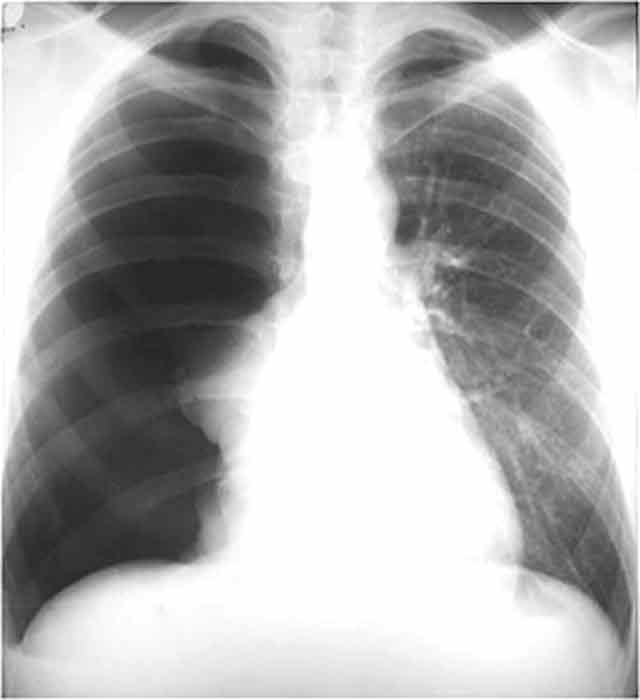

What is the name of the pathology as seen in this image?

Pneumothorax

What could the collapsed portion of lung tissue adjacent to the right side of the mediastinum also be known as?

Atelectasis